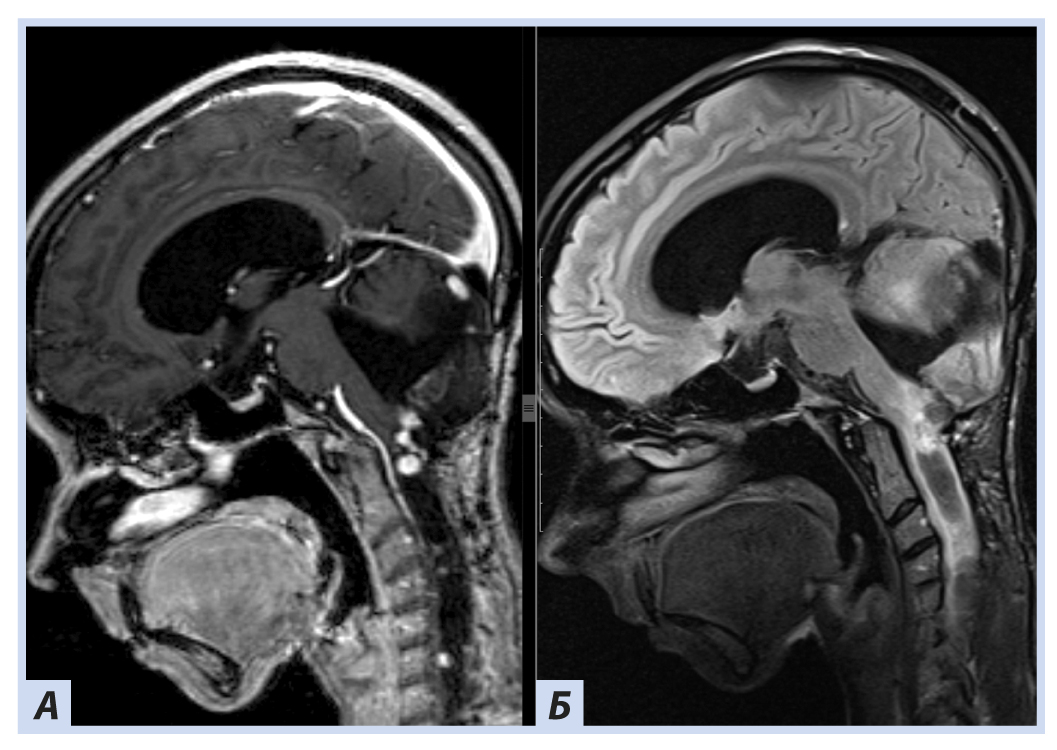

Лучевые методы. На МРТ-изображениях головного мозга выявлено характерное двустороннее поражение глаз (рис. 1), по данным КТ — с участками обызвествления (рис. 2). Также на КТ головного мозга были выявлены зона послеоперационных кистозно-глиозных изменений с наличием кисты и узла на уровне посттрепанационного дефекта в правом полушарии мозжечка, а также аналогичные зоны дорзальнее и в субкортикальных отделах; в левой гемисфере мозжечка определялись кистозные изменения (рис. 3).

Рис. 1. Пациентка П., 30 лет, с диагнозом «Болезнь Гиппеля−Линдау»: магнитно-резонансная томография головного мозга

Примечание. А, Б — Т2- и Т1-взвешенные изображения. В полости правой глазницы объемное образование с неоднородным МР-сигналом; В — постконтрастное Т1-взвешенное изображение, режим подавления сигнала от жира: определяется интенсивное, но гетерогенное контрастирование образования. Кровоизлияние в сетчатку справа.